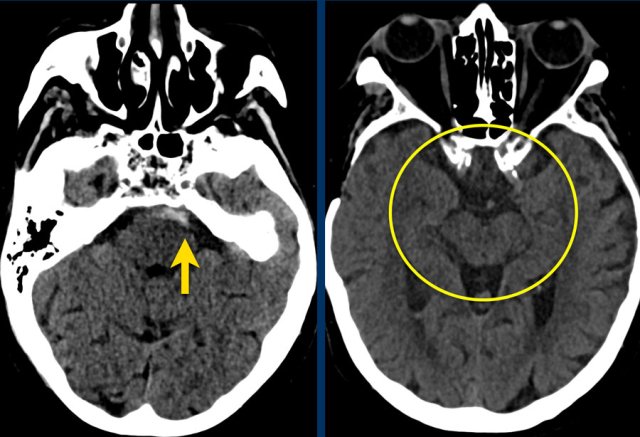

The images show a slightly hyperdense focus in the prepontine and interpedunclair cystern in a patient who presented with acute severe headache.

DSA did not show an aneurysm.

Here another example of a nonaneurysmal perimesencephalic SAH.

Left image: NECT showed a small amount of subarachnoidal blood anterior to the brainstem.

Right image: more cranially, the pentagon, ambiens cistern and the proximal part of Sylvian’s fissures, did not show any blood.

This is a typical presentation of nonaneurysmal perimesencephalic SAH.

The blood is solely located around the brainstem.